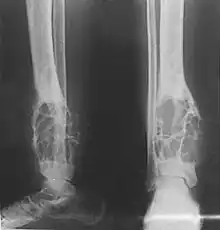

X-rays of the affected area show a well defined tumour in bone, with multiple lobules giving a "soap bubble" appearance.[9] MRI can provide a more useful guide to its severity.[9]